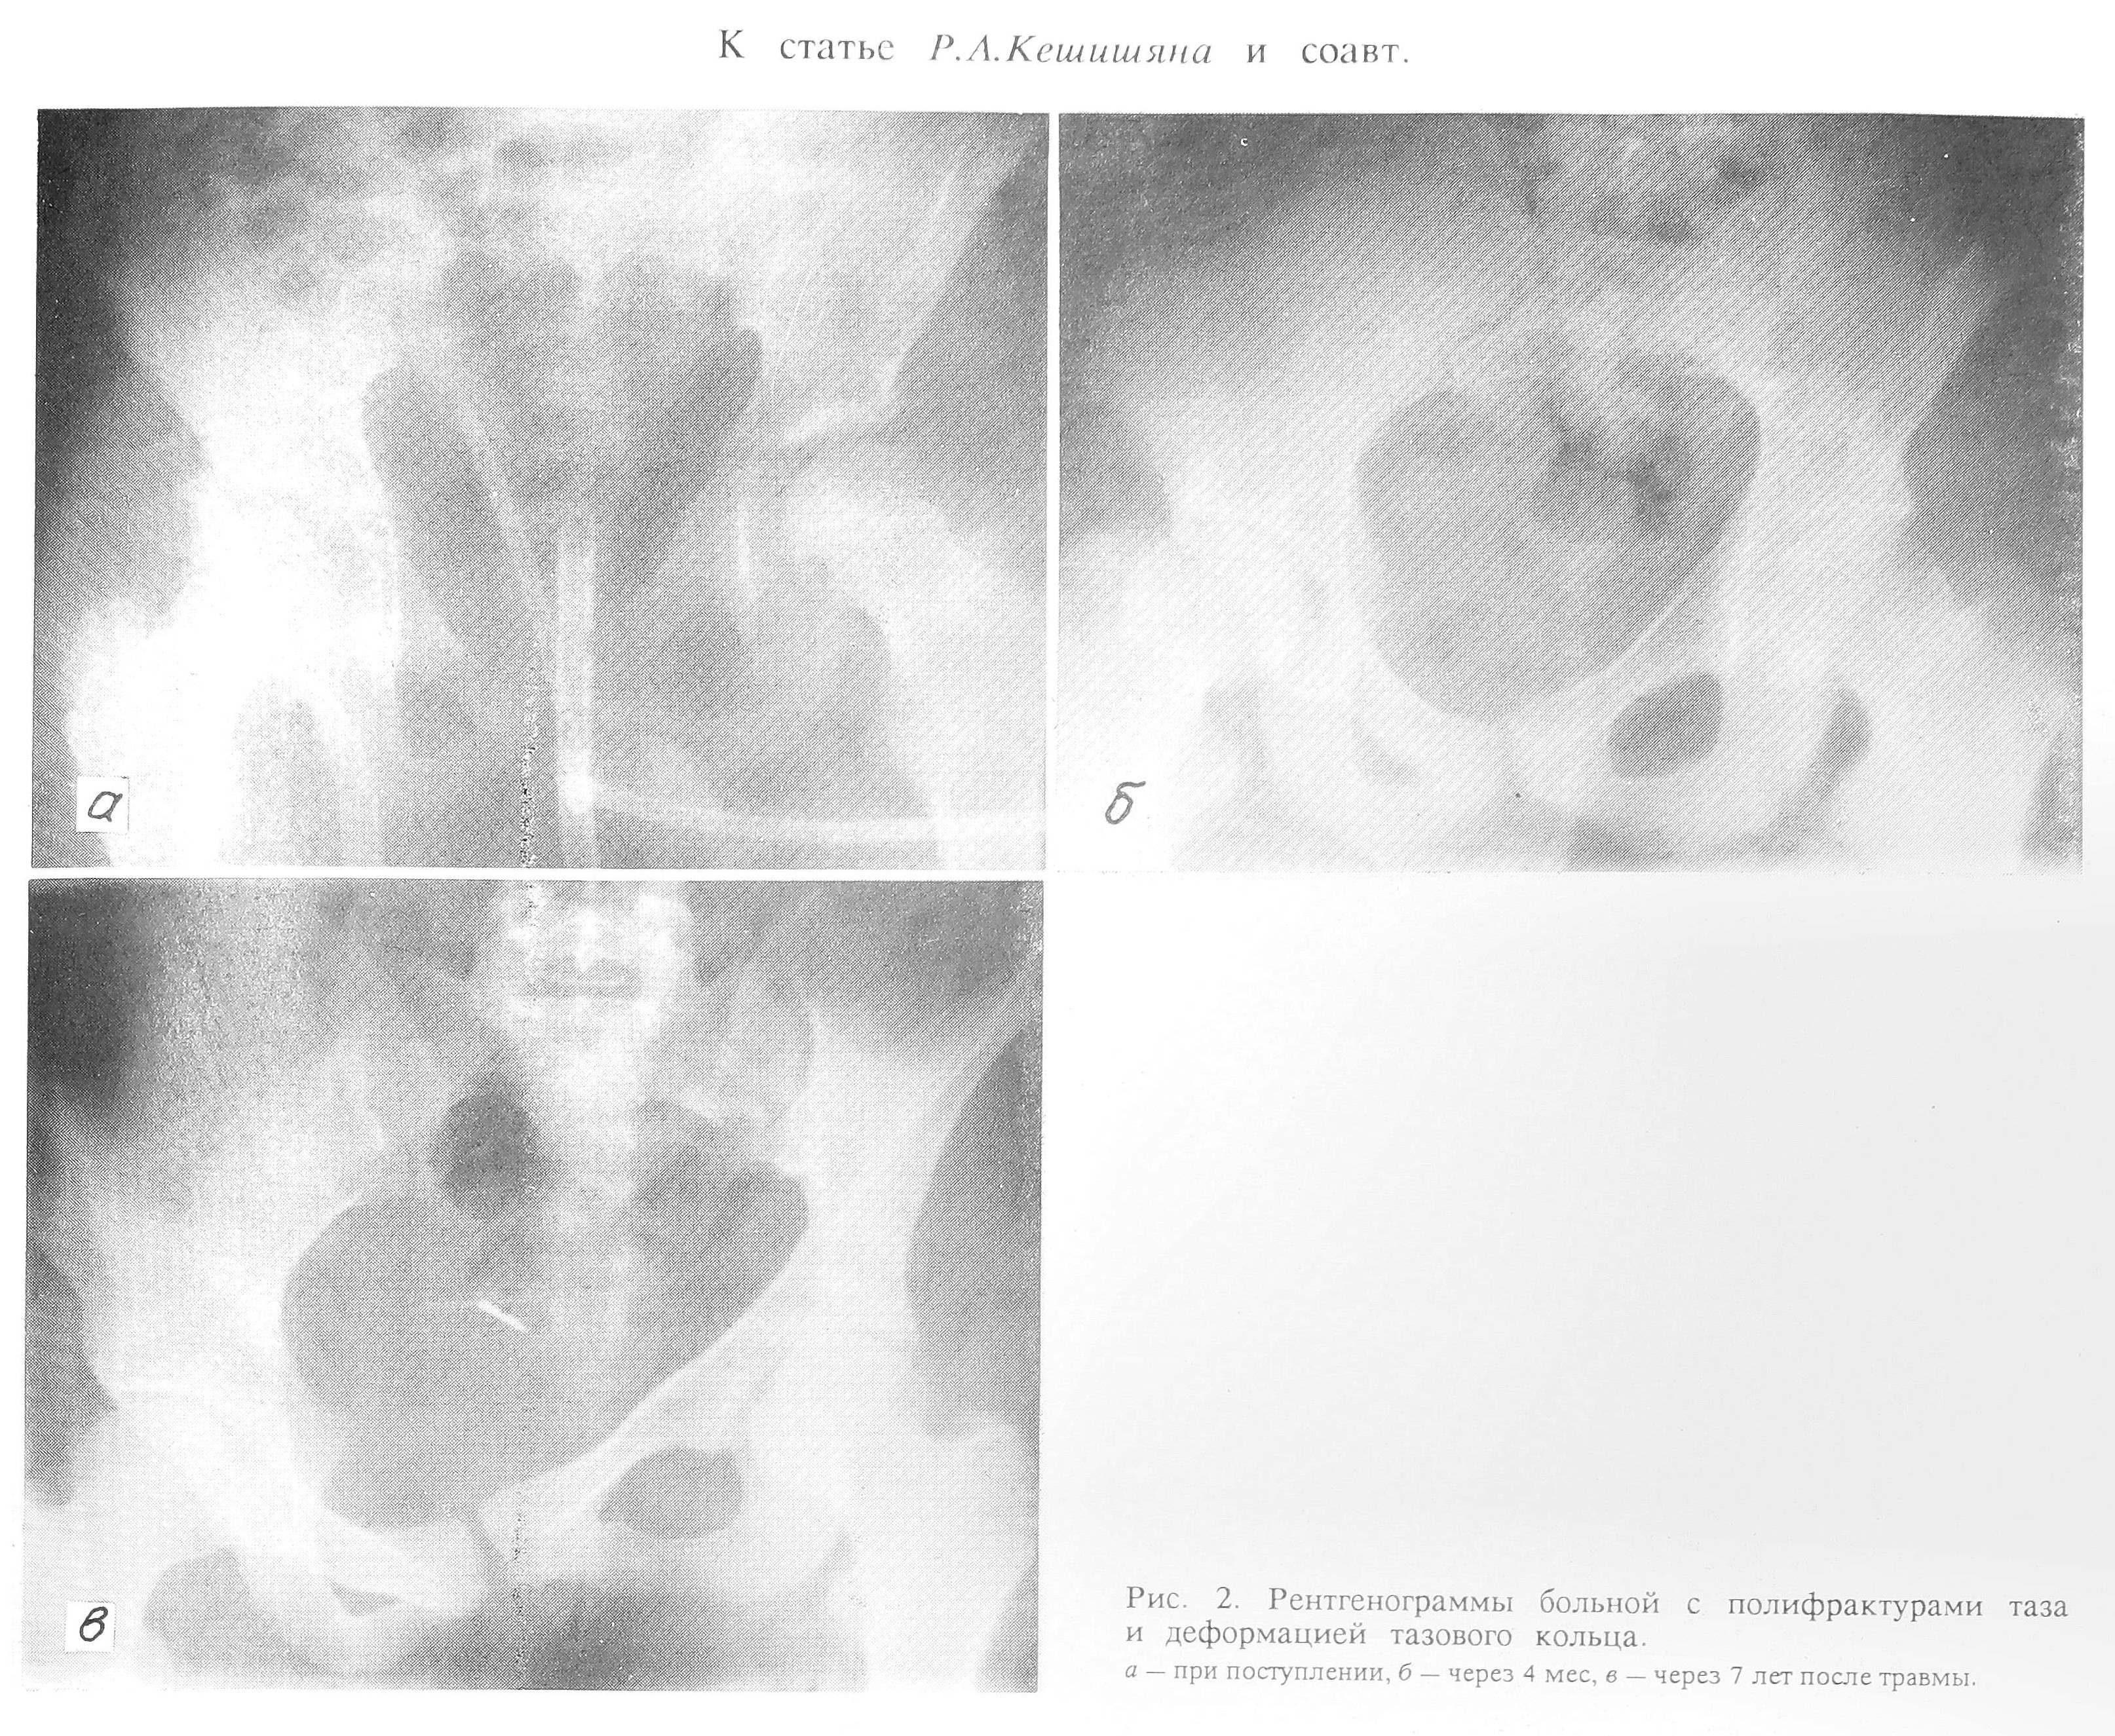

При катамнестическом обследовании во всех случаях констатирована консолидация переломов. Посттравматическая деформация тазового кольца у 5 больных носила стабильный характер, а у 6 было отмечено увеличение ИД (см. рис. 2 на вклейке).

Рис.2